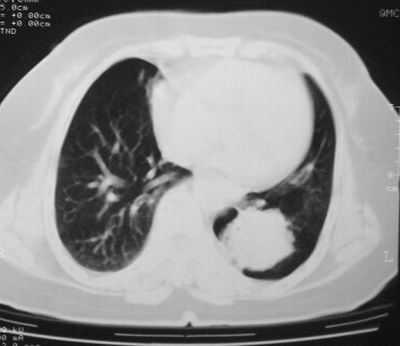

左下肺软组织块影,有分叶、毛刺、空泡及胸膜牵拉征,左下肺周围性肺癌。

左肺下叶周围型肺癌,支持!(软组织肿块+分叶+毛刺+空泡+胸膜凹陷征)

左下肺软组织密度影,可见分叶,边缘可见毛刺征,胸膜增厚,强烈要求左下肺周围型肺癌

左下肺后基底段实性肿块,周围有毛刺,病变周围有肺气肿,与降主动脉间有条带状影相连,病灶4年前查体发现,纵隔内未见肿大淋巴结。考虑.肺隔离症,建议增强扫描与周围型肺癌鉴别。